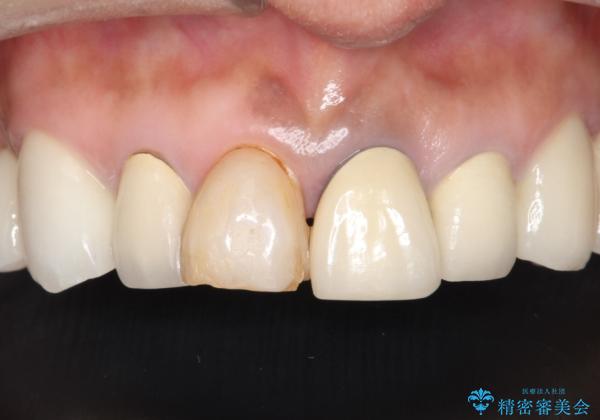

昔に治療された前歯が変色しているのと、形態が自然ではありませんでした。

前歯2本をオールセラミックにすることにしました。

オールセラミッククラウンにすることで、色と形態をきれいにすることができました。